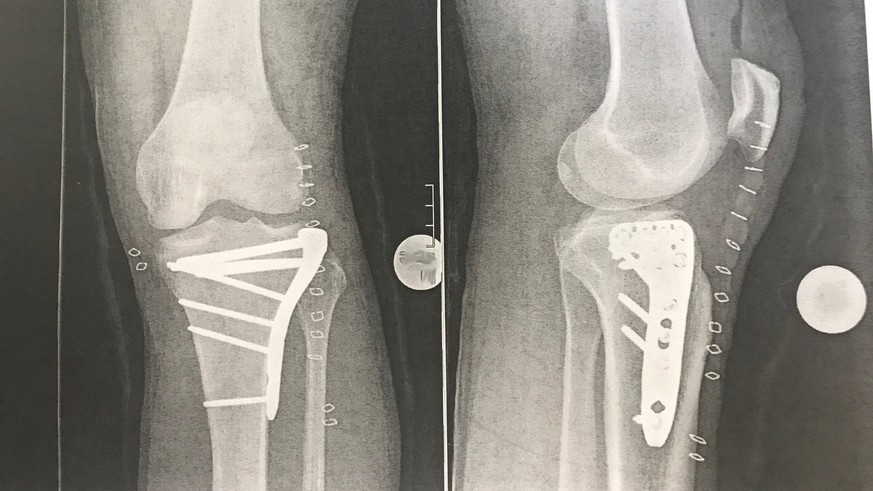

Die letzten Tage waren für Hammond alles andere als angenehm. Der Brite musste mehrmals unters Messer. «Nach schlaflosen Nächten und mehreren Stunden im Operationssaal freue ich mich euch mitzuteilen, dass mein ‹Swiss Army Knee› wieder zusammengeflickt ist», schreibt er auf seinem Blog. Es stelle höchstens ein Problem bei den Sicherheitskontrollen am Flughafen dar. Das Knie ist mit sechs Schrauben fixiert worden.